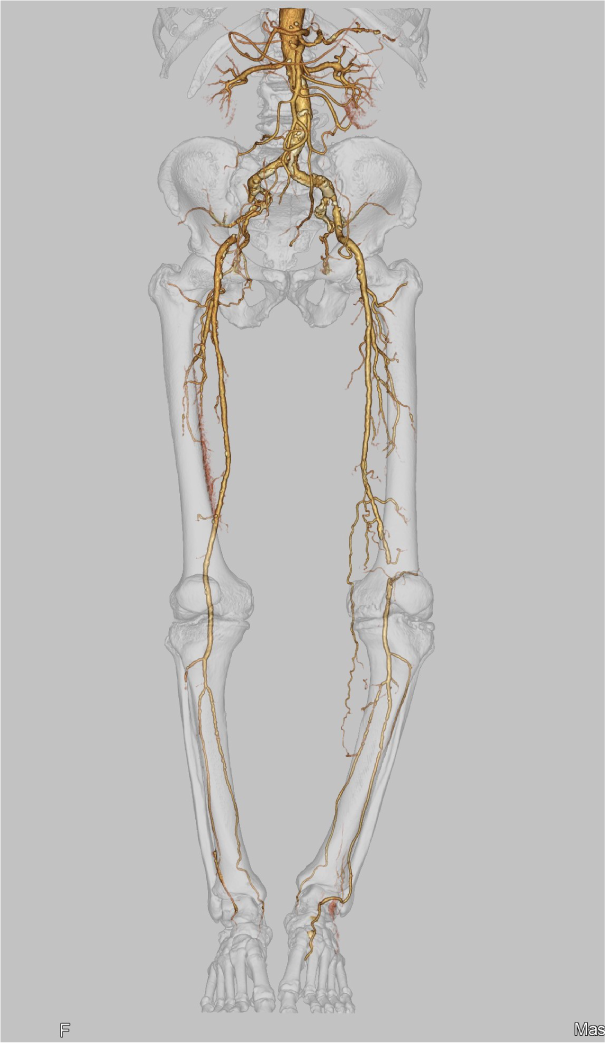

CANON(旧:東芝)社製の80列マルチスライスCTを設置し、胸部・腹部の撮影はもちろん、心臓CTや大腸CT、下肢3DCTといった専門性の高い撮影も行っています。最新のザイオワークステーションを用いて、3D画像作成、心臓解析、大腸の仮想内視鏡検査などを行っています。また、近隣の医療施設からのCT撮影依頼にも対応しており、日々たくさんご利用いただいております。被ばく線量の低減に配慮するとともに、患者さんに合った適切な線量で撮影を行うように心がけています。

前腕CT画像 下肢CT画像

シーメンスヘルスケア社製のCアーム装置を使用し、PTA(経皮的血管拡張術)や下肢動脈に対するEVT(血管内治療)、心臓カテーテル検査など、さまざまな検査・治療を行っています。手術室で行うため、被ばく線量に十分配慮しながら、医師を初めとする様々な医療スタッフと連携し、チーム医療で取り組んでいます。